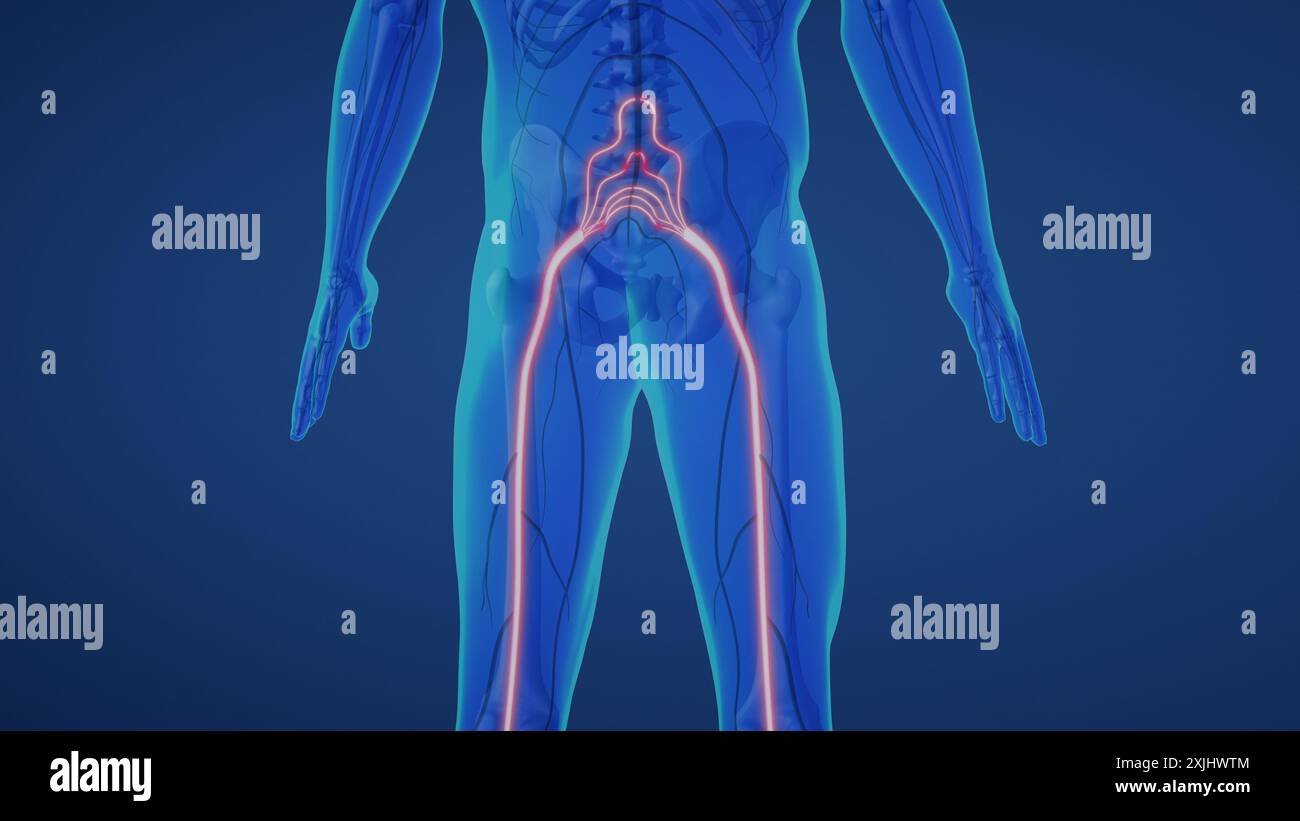

Douleur du nerf sciatique dans le bas du corps Banque D'Imageshttps://www.alamyimages.fr/image-license-details/?v=1https://www.alamyimages.fr/douleur-du-nerf-sciatique-dans-le-bas-du-corps-image613820164.html

Douleur du nerf sciatique dans le bas du corps Banque D'Imageshttps://www.alamyimages.fr/image-license-details/?v=1https://www.alamyimages.fr/douleur-du-nerf-sciatique-dans-le-bas-du-corps-image613820164.htmlRF2XJHWTM–Douleur du nerf sciatique dans le bas du corps